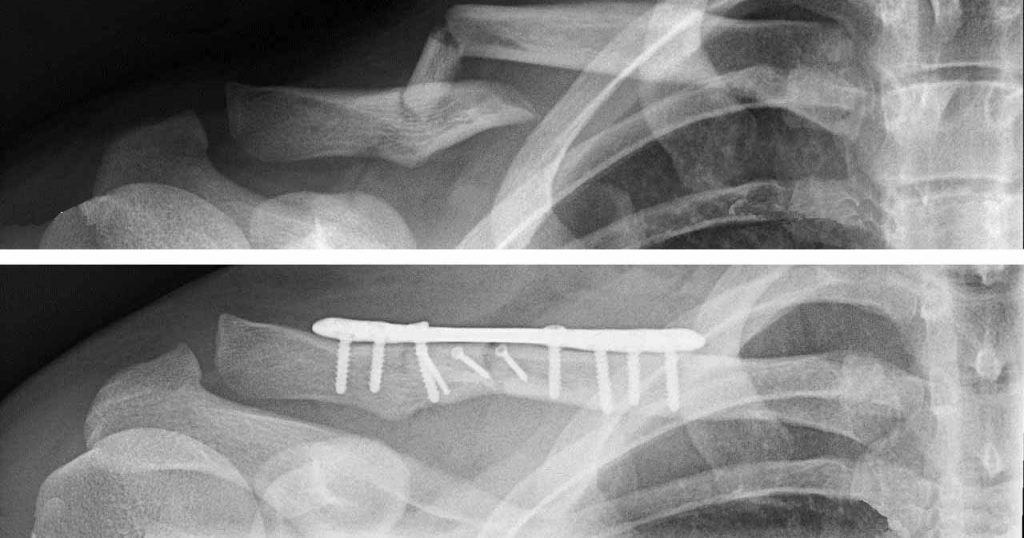

Unfallchirurgie

Akute Verletzungen des Bewegungsapparates

und deren Folgen

- Typische Verletzungen: Knochenbrüche Bandverletzungen Sehnenverletzungen Muskelrisse Gelenksluxationen Sport- und Freizeitverletzungen

- Behandlung: Akutversorgung nach Verletzungen operative Stabilisierung bei Bedarf Nachbehandlung und Rehabilitation Behandlung von Spätfolgen

- Ziel: Ziel der unfallchirurgischen Behandlung ist es, Verletzungen des Bewegungsapparates optimal zu versorgen und eine sichere Wiederherstellung von Funktion, Stabilität und Belastbarkeit zu ermöglichen.